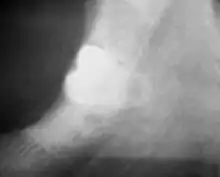

Wisdom tooth with close association to the inferior alveolar nerve.

• Lower wisdom tooth is shown to be close to the inferior alveolar canal radiographically:[6]